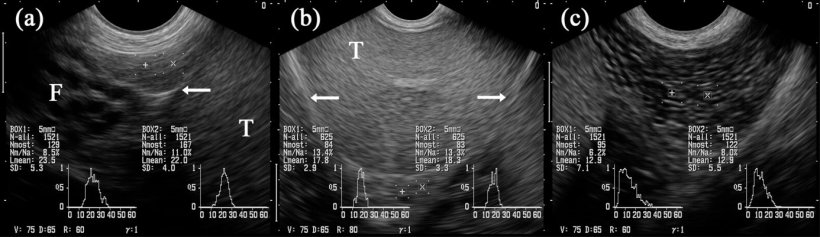

I testicoli possono esser ecografati longitudinalmente o transversalmente (figura 2A e B). Per determinare la circonferenza del testicolo, si devono usare immagini trasversali. Il tessuto testicolare sano ha una ecogenicità media e presenta una ecotessitura omogenea, con la rete testis iperecogenico nel centro del testicolo (figura 3A e B).

In genere, il tessuto dell'epididimo ha ugualmente una tessitura ecografica omogenea e regolare, essendo più sottile nella testa e nel corpo, e un poco marmorizzata nella coda (figura 5A-C). Tuttavia, l'ecogenicità determinata dall'"analisi di scala di grigio", è data come il valore grigio medio, differendo leggermente tra i 3 segmenti, assieme ai cambi d'immagini ottenute confrontando prima e dopo la raccolta del seme del verro (Kauffold et al. 2011).